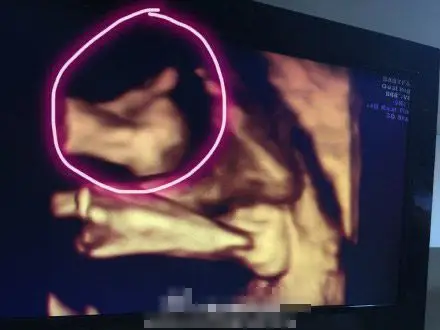

2010首页 滚动新闻 原标题:林志颖晒双胞胎儿子b超照 弟弟孕肚中比赞